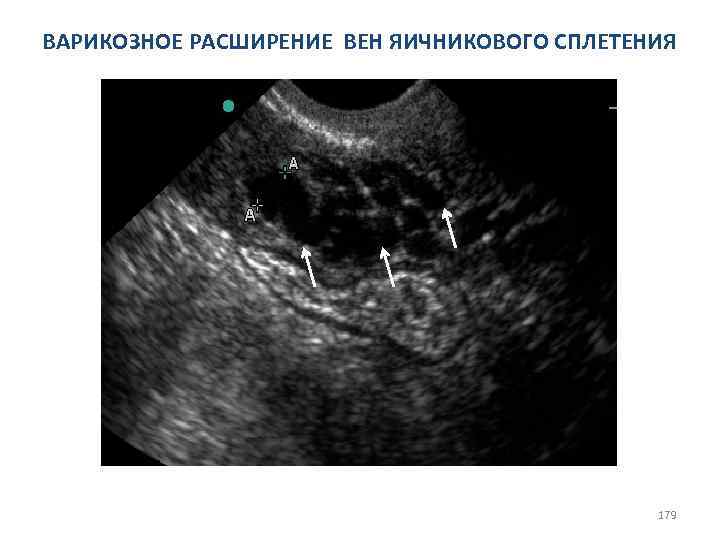

Сонографические варианты варикозного расширения тазовых вен: I. Магистральный— длинные трубчатые, извитые или ретортообразные, непульсирующие структуры диаметром от 5 мм до 15 мм. Левосторонняя локализация превалирует. II. Рассыпной— в виде ячеистых, губчатых анэхогенных многокамерных (полилинейных) образований. III. Сочетанный (=тотальный)—объединяет магистральный и рассыпной варианты. 177

Сонографические варианты варикозного расширения тазовых вен: Рассыпной вариант при варикозе: 1. параметральных вен (plexus uterovaginalis) - 40%; 2. яичникового сплетения (plexus pampiniformis ovarii) – 60%; Сочетанный (=тотальный) вариант при варикозе: 1. параметральных вен (plexus uterovaginalis); 2. яичникового сплетения(plexus pampiniformis ovarii); 3. внутренней подвздошной вены(v. iliaca interna); 4. прямокишечного сплетения(plexus rectalis); 5. крестцового сплетения (plexus sacralis). 178

ВАРИКОЗНОЕ РАСШИРЕНИЕ ВЕН ЯИЧНИКОВОГО СПЛЕТЕНИЯ 179